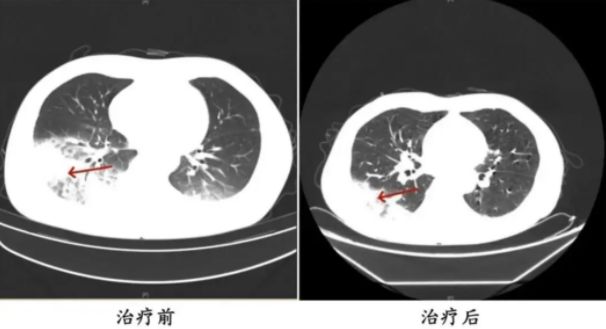

胸部CT显示李先生的左肺已出现大面积白色影像,几乎占据一半肺部。经过肺泡灌洗NGS检测,最终确认“罪魁祸首”是嗜肺军团菌。

李先生肺部治疗前与治疗后的对比

周先生治疗前后的肺部CT影像。图源:央视网